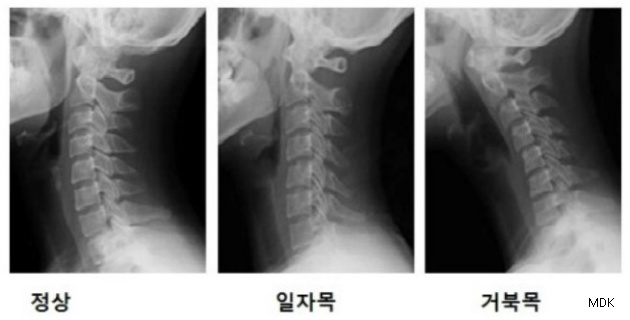

국민건강보험 일산병원 재활의학과 이장우 교수는 “일자목증후군은 잘못된 자세와 동작이 원인이 되고 이러한 요소들이 장기간 축적되어 골격의 변형까지 일으키는 질환"이라며 “근래 컴퓨터나 스마트폰 사용이 일상화 되면서 발생 연령이 점차 젊어지고 있다”고 설명했다.

‘일자목증후군’을 방치할 경우 “목 부위 통증뿐 아니라 두통이나 어깨 통증까지 유발할 수 있고 나이가 들면 구조물들의 비가역적 변화를 야기해 통증이 더 심해질 수 있다"며 "목 척추나 디스크 등의 퇴행성 변화를 초래하여 추간판탈출증이나 심한 경우 경추척수증과 같은 신경증상을 일으킬 수 있다”고 설명했다.